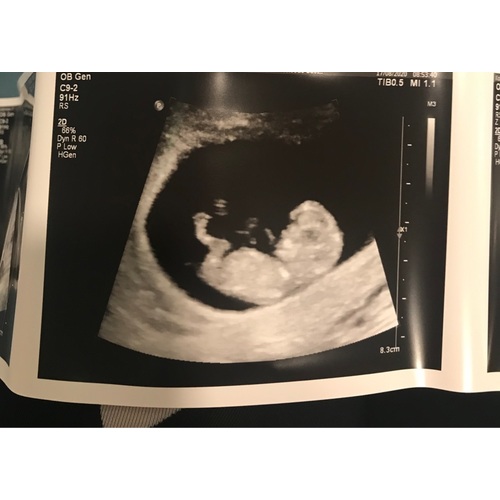

Hier ook 13 maart uitgerekend! Heel mooi om te zien hoe bewegelijk al en prachtig beentje. Nog wel de nipttest volgende week ivm leeftijd...vandaag 43 jaar geworden 🥰